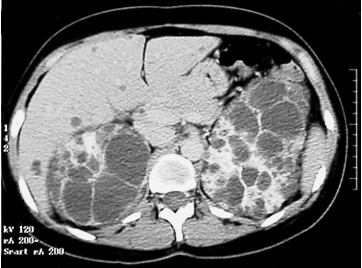

A 35-year-old male presents to the office with bilateral abdominal pain and hematuria, progressing during the past 2 months. He states that the pain is located over his flank and is relatively unchanged based on position or time of the day. He has not taken any over-the-counter medications, but heating pads provided no relief. Vital signs reveal a blood pressure of 150/90 mmHg. Physical and osteopathic examination reveals abdominal fullness, with maximal tenderness to palpation at the level of T10 and a discrete somatic dysfunction at that level. Costovertebral angle tenderness is mildly present bilaterally. An abdominal CT scan is obtained as shown in the exhibit. The patient states that his father also had "cysts on his kidneys" but passed away suddenly at 42 years of age.

Which of the following is true regarding this person's disease state?